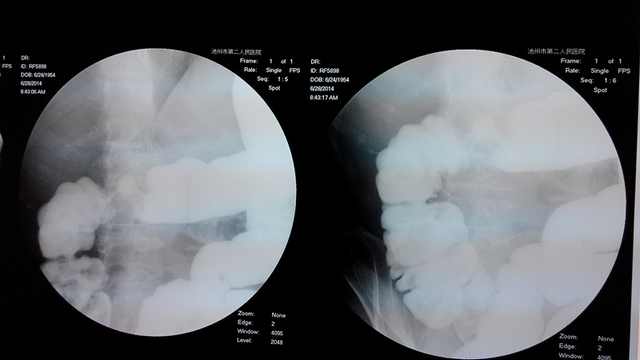

该患者60岁,近期感腹部不适,在家人的陪伴下来我院就诊,经过门诊初步检查为结肠肿瘤,为进一步治疗遂入住我院外科。入院后经过完善的辅助检查,叶临生主任医师决定为其行腹腔镜辅助根治性右半结肠切除术,经过3个多小时的努力,在麻醉科和手术室护士的齐心协力配合下,叶临生主任医师团队顺利完成了难度较高的腹腔镜辅助根治性右半结肠切除术,术后切除的标本发现肿瘤约6*8cm大小。

与传统的开腹手术比较,腹腔镜微创手术具有创伤小、恢复快、住院时间短的优势,患者只有微小不适感,腹壁上也只有四个0.5cm长的浅痕及一个脐上方3cm的疤痕。

腹腔镜下结、直肠癌根治术在欧美发达国家已经普及,与传统开放手术比较,腹腔镜下根治切除术具有明显的优势:损伤小、恢复快、镜下视野清楚、腹部美观性好等,而且手术效果和术后5年生存率与开腹手术相比无统计学差异,甚至优于开腹手术。近年来国内大型医院纷纷开展该项技术。然而,腹腔镜结、直肠癌根治术较为复杂,技术要求高,要求医生既要有较高的腔镜外科技术,又要有较高的胃肠外科技术,现本市只有少数医院能够开展此类难度较大手术。该例患者手术的成功标志着我院外科腔镜手术水平又上了一个新的台阶。